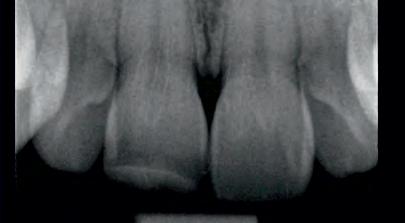

A 30-year-old patient, with a negative medical history, came to the clinic requesting the replacement of the previous composite reconstruction performed 10 years earlier following a trauma to UR1.

On clinical examination, UR1 was responsive to viability testing, and did not present periapical lesions on the radiograph performed on the same day (Figure 1). UR1 was discoloured and in a more palatal position than the contralateral central UL1 (Figure 2). The aesthetic analysis highlighted an asymmetry of the gingival zenith between UR1 and UL1. Through the use of a periodontal probe, after plexus anaesthesia, the altered passive eruption of the type IA junctional epithelium was confirmed according to the classification of Coslet et al. (Figure 3).

FIGURE 1: Radiograph without periapical lesion.